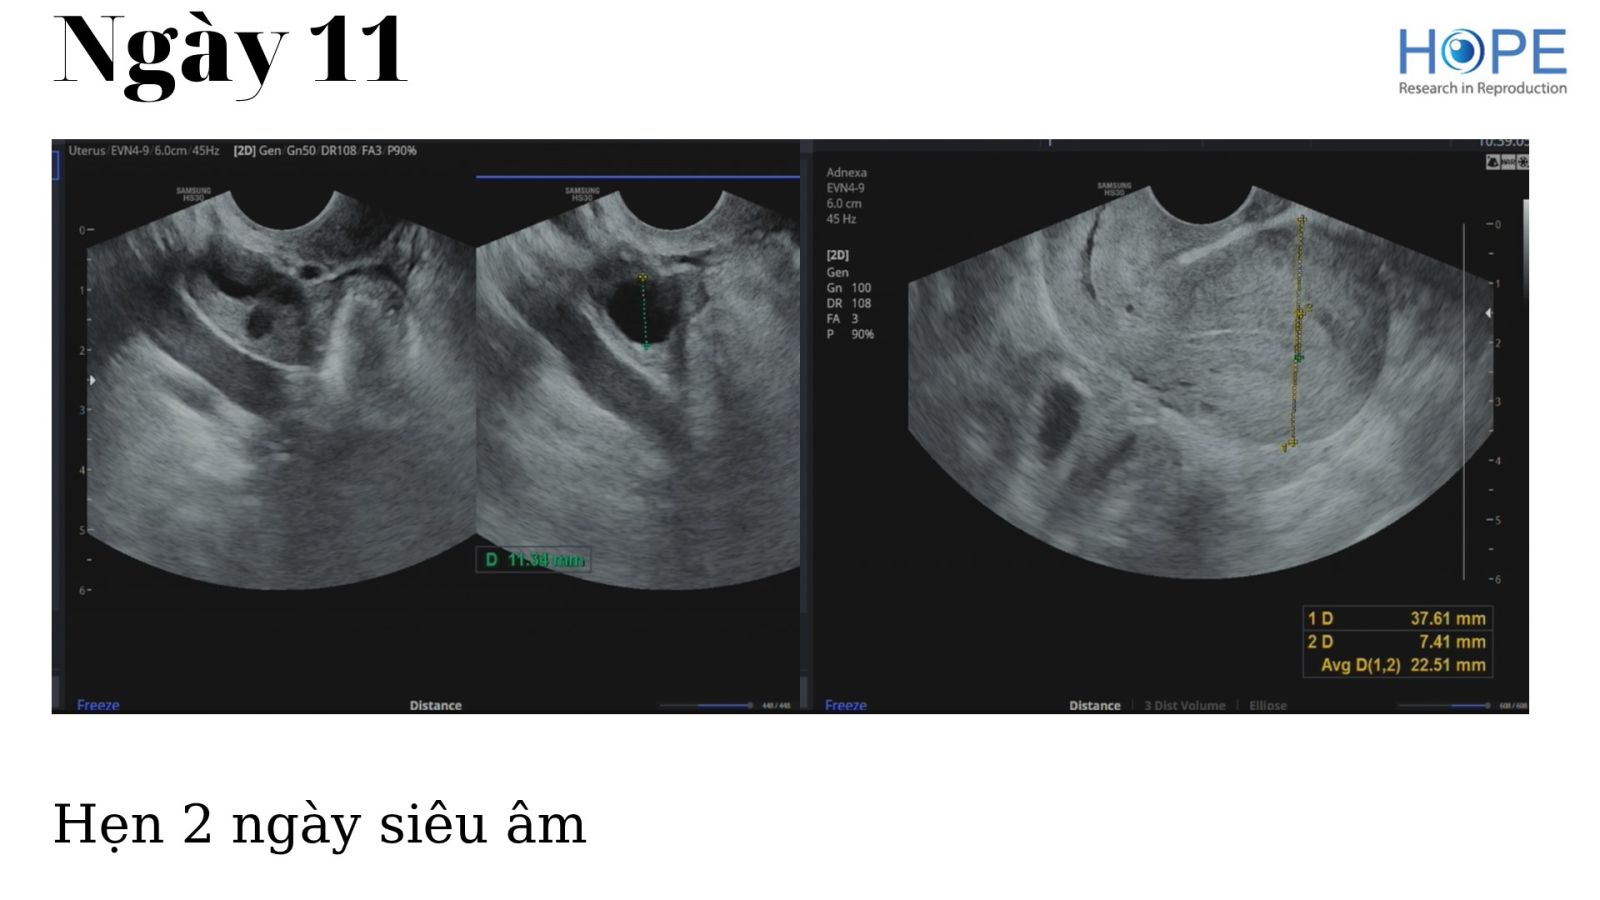

Các phác đồ kích thích buồng trứng nhẹ để IUI –  cách theo dõi kích thích buồng trứng

BS Lê Thị Hà Xuyên - IVFMD Phú Nhuận